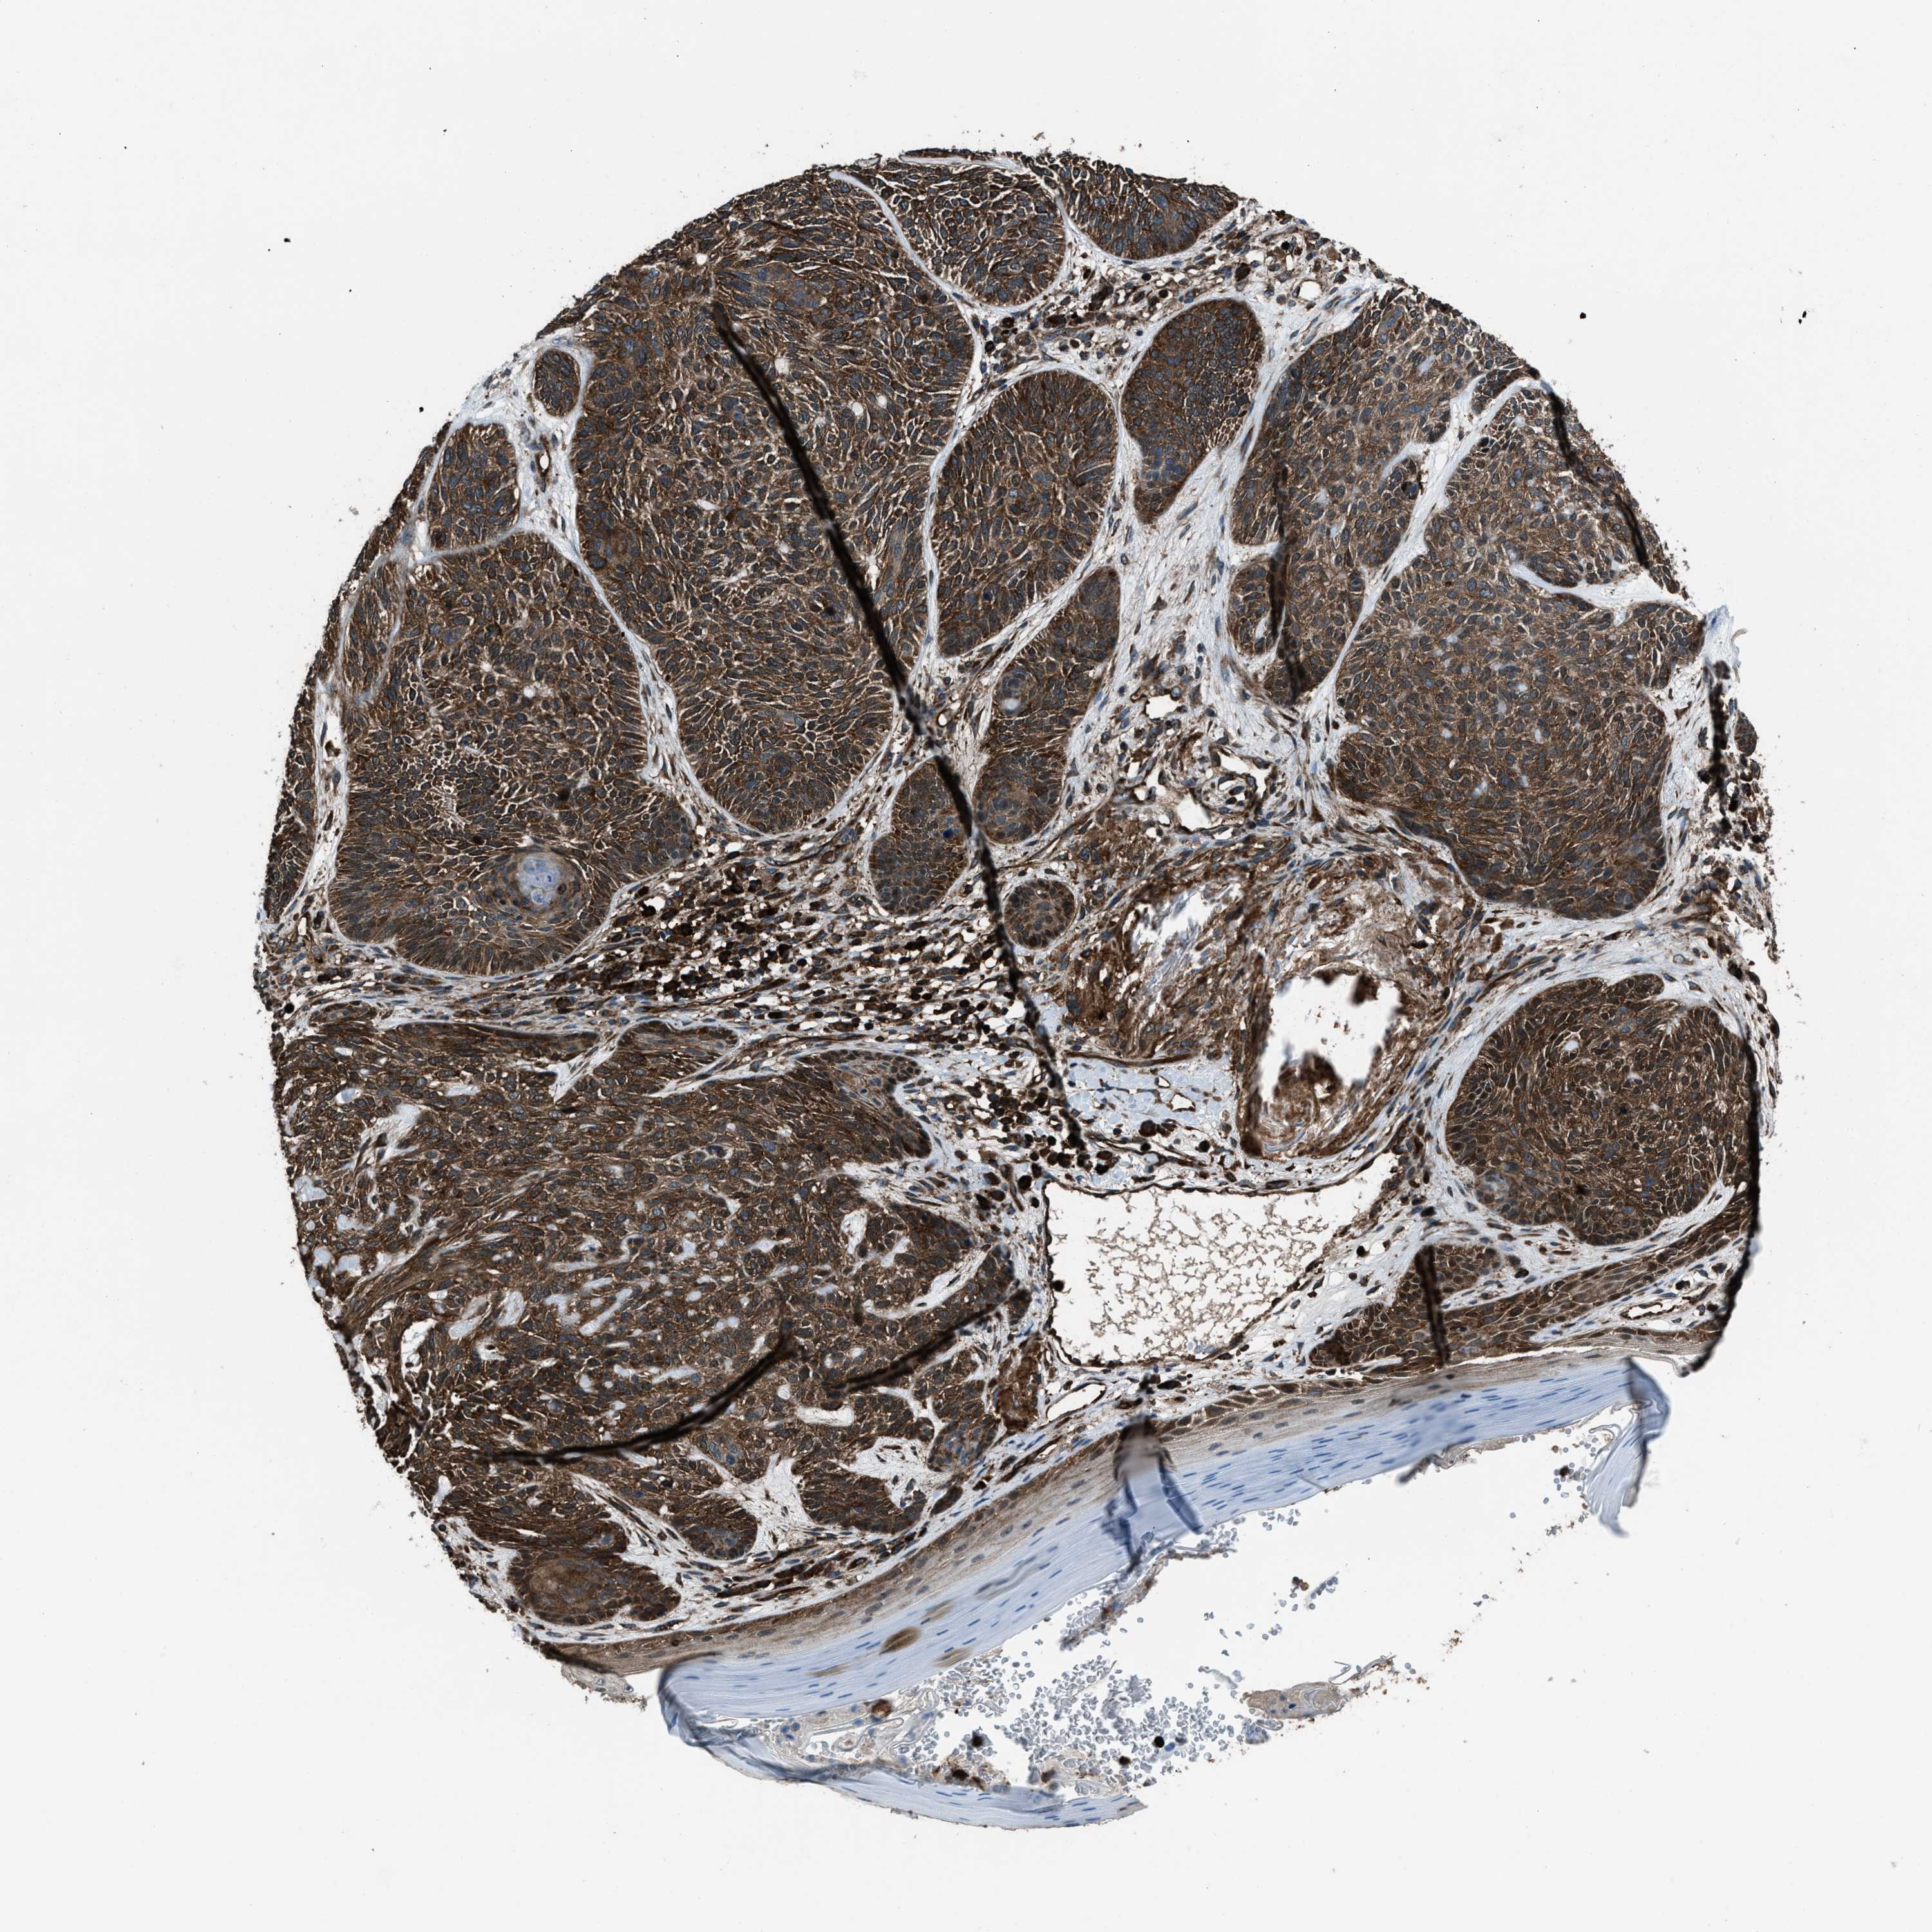

Basal cell and squamous cell cancer

SKIN CANCER - Protein expressioni

A mouse-over function shows sample information and annotation data. Click on an image to view it in a full screen mode. Samples can be filtered based on level of antibody staining by selecting one or several of the following categories: high, medium, low and not detected. The assay and annotation is described here.

Each image is clickable and will lead to virtual microscopy that enables deeper exploration of all samples and also displays staining intensity scores, fraction scores and subcellular localization as well as patient and tissue information for each sample.

Antibody HPA019346

Staining

High

Strong

>75%

Location

Nuclear

Basal cell carcinoma